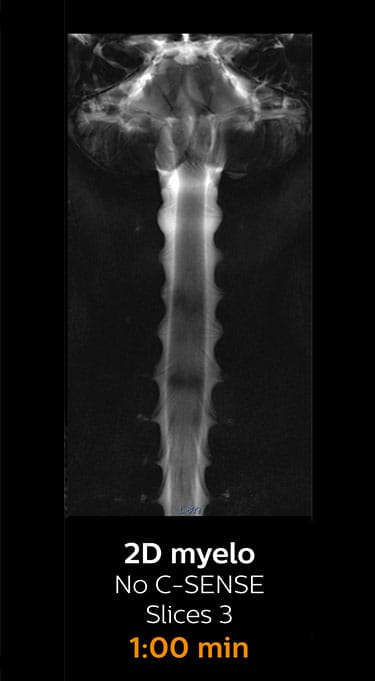

Fast MRI of lumbar spine

With Compressed SENSE, the scan time for the routine lumbar spine examination at KNC was reduced from 11:41 to 8:17 minutes,

which corresponds to 34% reduction.

MRI examination of lumbar spine with Compressed SENSE

MRI examination of the lumbar spine with Compressed SENSE

Ingenia 3.0T CX

Scan time 8:17 min. (was 11:41 min. without Compressed SENSE)